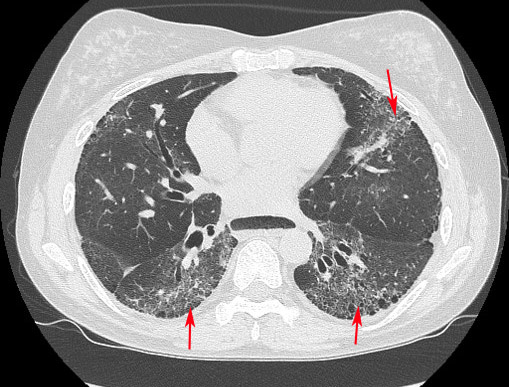

全身性硬化症是一種少見的自體免疫疾病,在自體免疫疾病中死亡率最高,患者平均死亡率是同年齡層族群的2.7倍。此病好發於女性,發病原因仍不明確,目前已知長期暴露於矽粉塵環境或化學溶劑可能誘發疾病。初期症狀是在天冷或接觸冰冷物體時,手指會變白或變紫,回暖後恢復紅潤,稱作雷諾氏現象。隨著病情進展,皮膚逐漸變硬、變緊,內臟器官也可能出現纖維化,導致呼吸急促、胃食道逆流,甚至引發肺纖維化和肺動脈高壓等嚴重併發症,肺纖維化是病人最主要的死亡原因,因此及早診斷治療並找出高風險族群至關重要。

全身性硬化症診斷仰賴臨床症狀與抽血檢測自體免疫抗體,臺中榮總自2020年引進新型抗體檢測技術,由原本可檢測3種抗體,擴增至8種,診斷敏感度由60%提升至80%,再搭配傳統抗核抗體檢查(ANA)比對排除偽陽性問題,幫助初期症狀尚不明顯的病人及早治療、控制病情。醫療團隊也透過檢測自體免疫抗體預測病人肺部受影響的機會,發現同時帶有Scl-70抗體與Ro52抗體者,約8成會合併肺纖維化,屬於高風險族群,相關成果於2023年發表於國際期刊《Clinica Chimica Acta》。